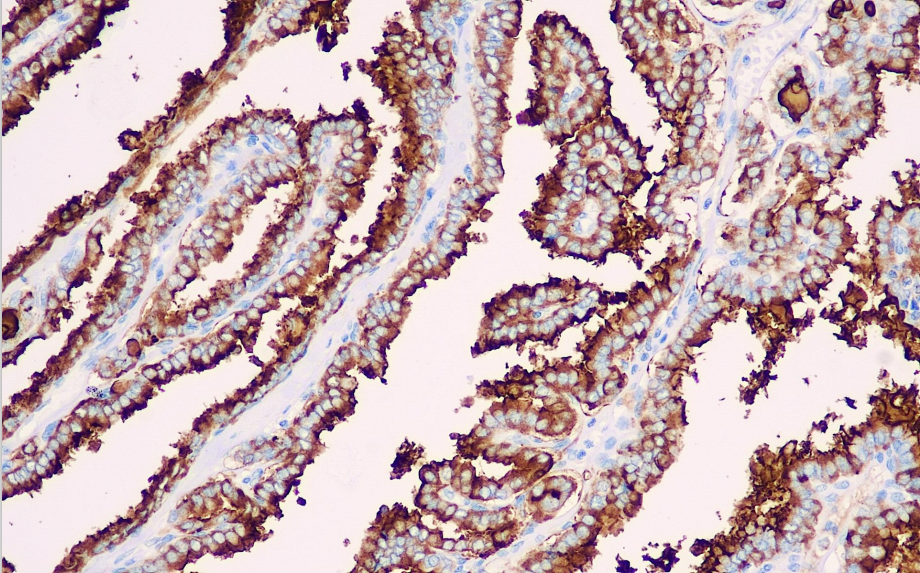

Positive control: Papillary thyroid carcinoma

Thyroglobulin is a 330 kDa glycoprotein synthesized by thyroid follicles. This antibody exhibits high tissue specificity and is primarily used in the study of various types of primary and metastatic thyroid follicular epithelial carcinomas.

THY antibody reagents can specifically bind to THY molecular antigens. Immunohistochemistry kits containing THY antibody reagents are suitable for the auxiliary diagnosis of primary and metastatic thyroid follicular epithelial carcinoma.